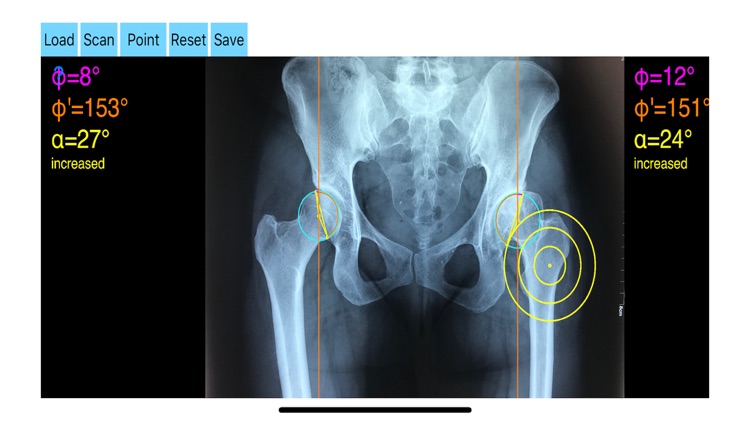

AcetabularAnteversionApp screenshot-2

Acetabular version is conventionally evaluated on CT scans but excessive radiation doses associated with routine use of computed tomography (CT). An objective radiographic tool which provides measurements comparable in accuracy to CT measurements has been developed by Dr. Hefti (Nomogram).Tedious and time-consuming calculation has to be done in simple X-rays in order to calculate the acetabular anteversion. The primary goal of this App is to help determine radiographic values of acetabular anteversion in a practice in a blink of an eye and avoiding CT scans.

-By marking certain points in a simple standard AP pelvic radiograph, geometric parameters are being calculated. The App computes the acetabular anteversion based on a pelvic AP radiograph. The angle of anteversion is calculated through the formula according to Heftis nomogram. The acetabular orientation (anteversion/retroversion) is determine by the app by the measurement of the angles between the center of the femoral head and the anterior (φ) and posterior (φ’) acetabular rim.

Once you choose correctly the anterior and posterior acetabular rims the app calculates the acetabular anteversion based on nomogram.

-The data are printed over to screen so each case can easily assessed